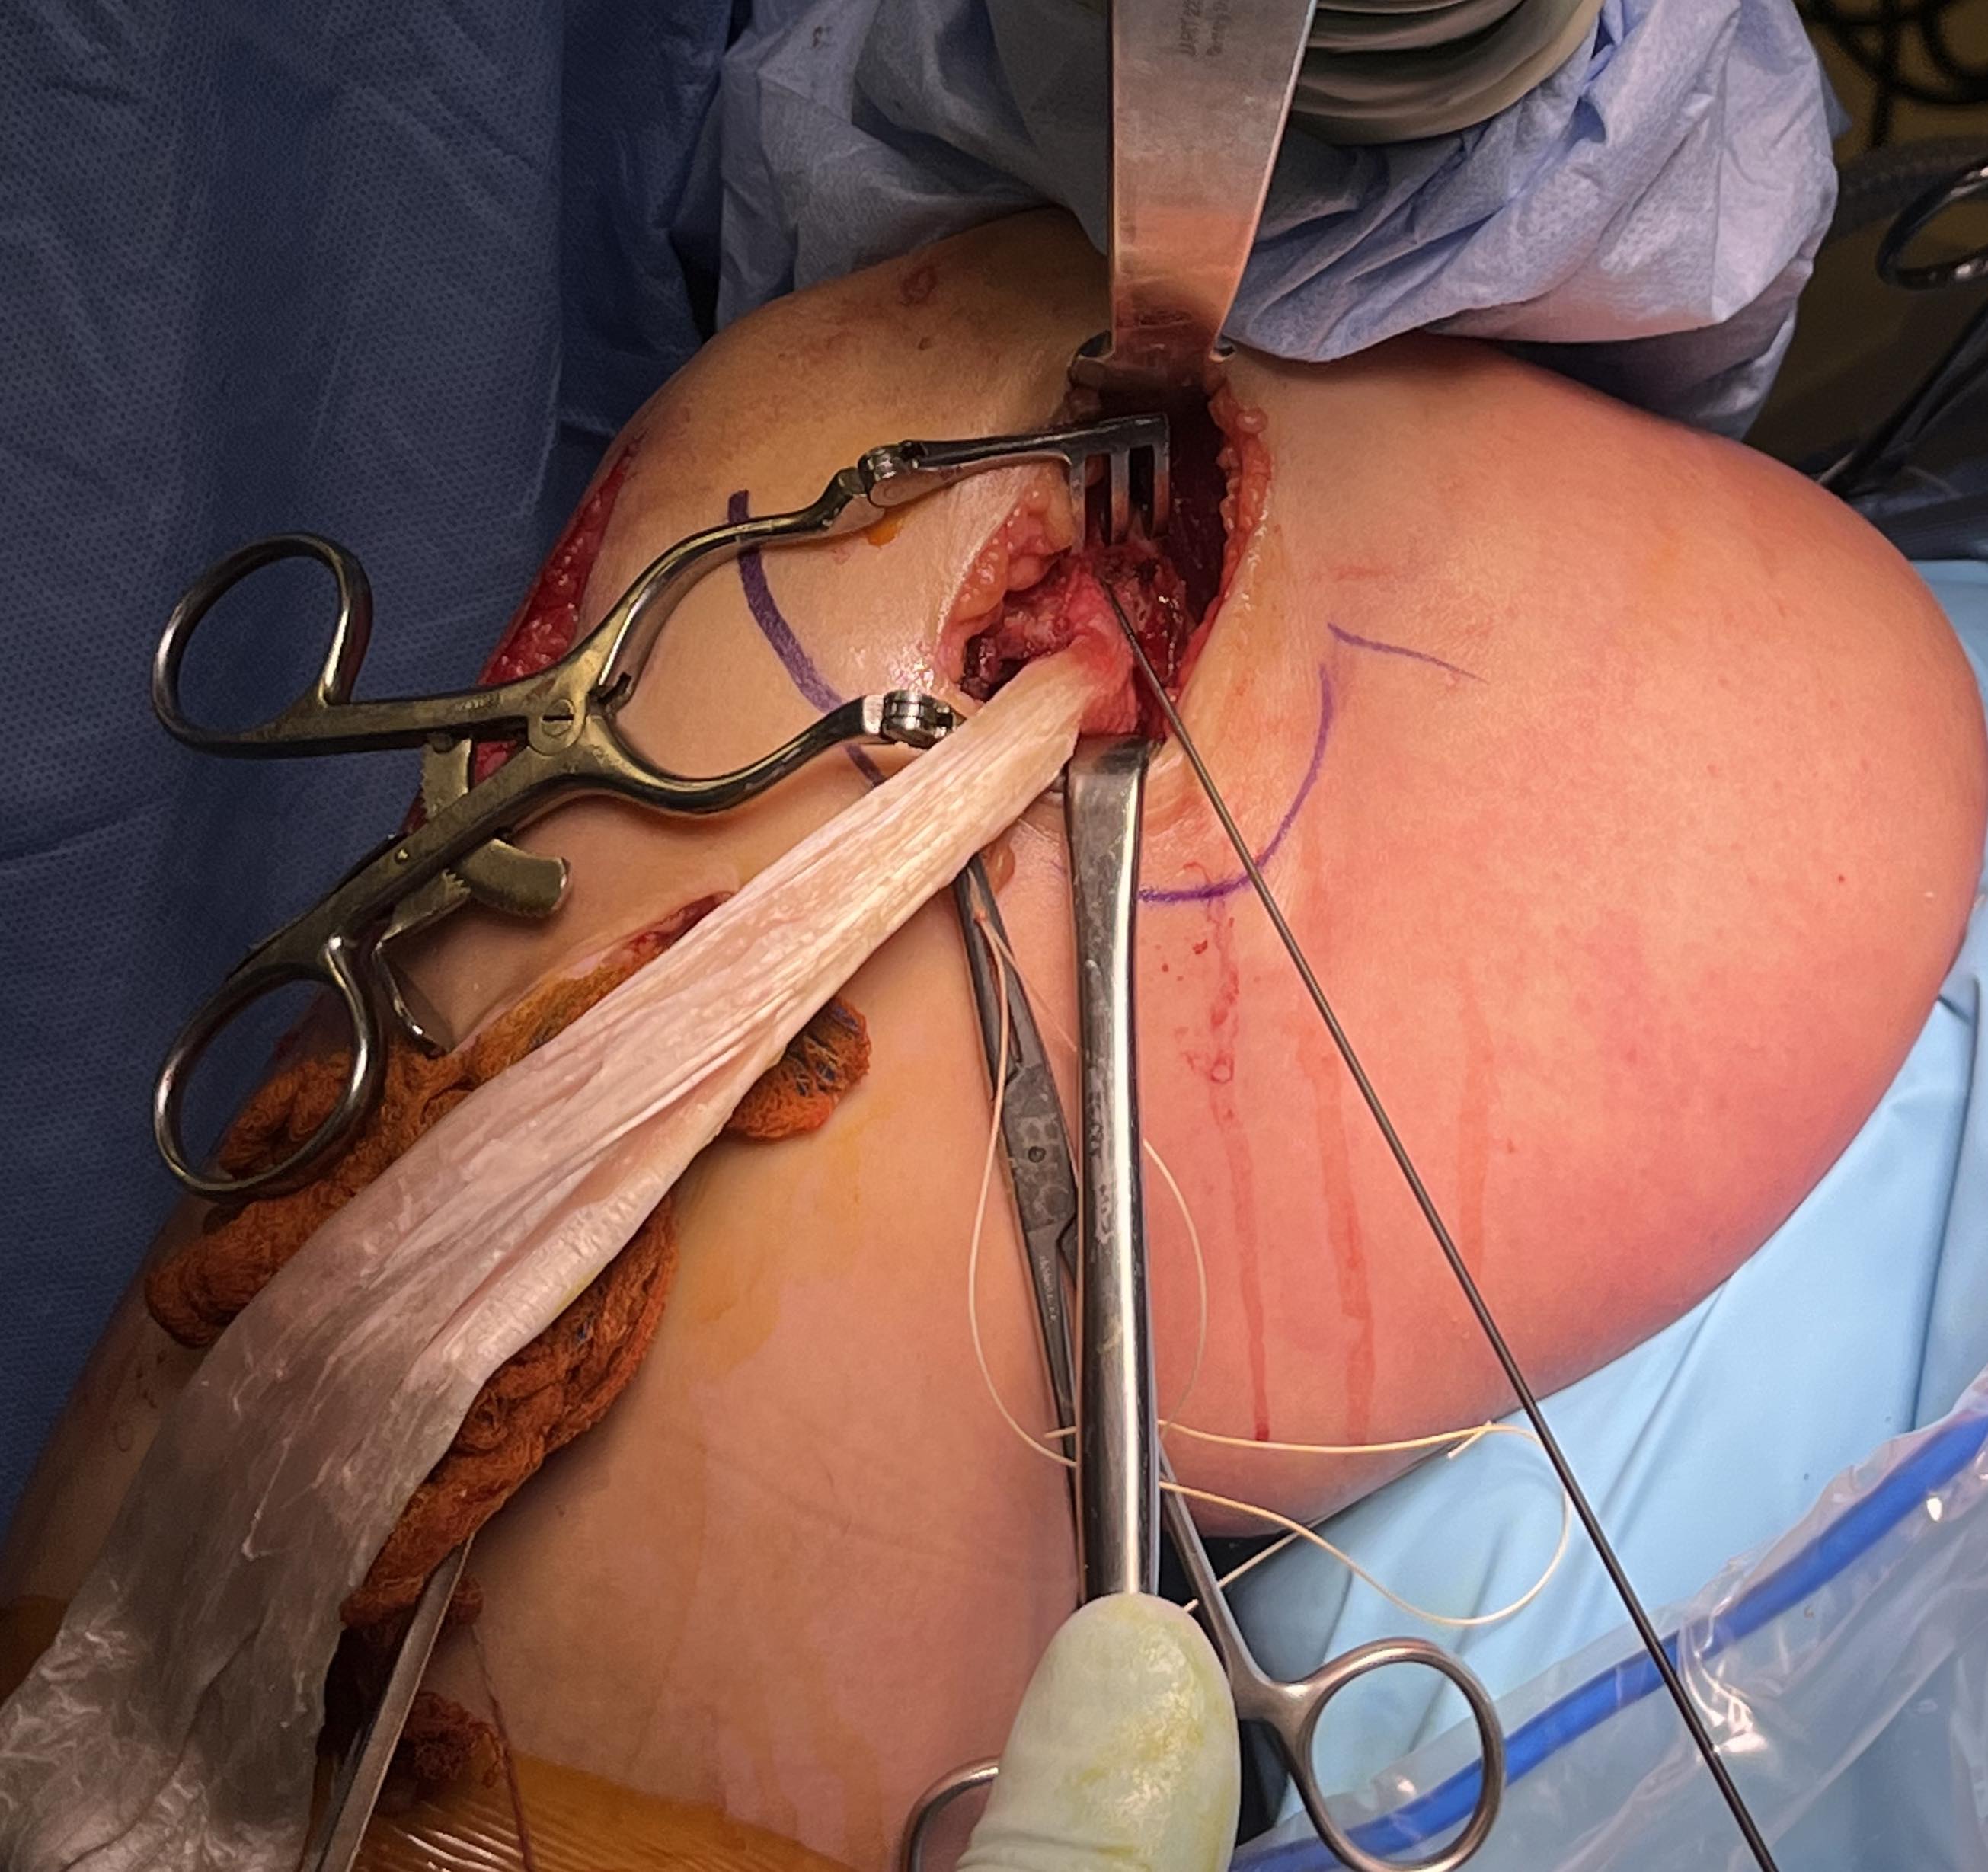

Surgical Approach to Medial Knee

Position

- knee flexed to 90o, over bolster

- tourniquet

- sandbag under hip

Incision

- hockey stick medial incision

- halfway between borders of tibia

- extends proximally to adductor tubercle

- distally to pes anserinus

Superficial dissection

- protect the saphenous nerve and small saphenous vein

- emerges from between sartorius and gracilis

- divide medial patella retinaculum from VMO down

- divide sarfascia over pes anserinus

- reflect pes anserinus inferiorly

Deep dissection

- elevate VMO to identify proximal insertion of superficial MCL

- expose superficial MCL running from medial epicondyle down to tibia under pes

- popliteal oblique ligament and semimembranosus are posterior to MCL

- can expose posterior capsule by carefully reflecting medial gastrocnemius posteriorly